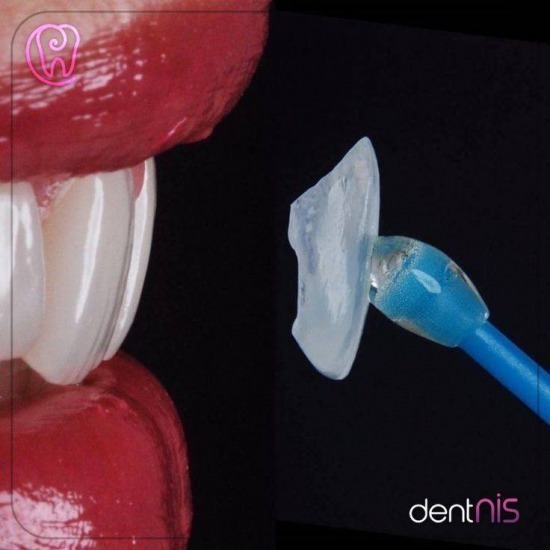

รากฟันเทียมเกิดจาการใช้วัสดุไทเทเนียม เข้าไปฝั่งอยู่ในกระดูกขากรรไกร และทำให้เกิดการสร้างกระดูกล้อมรอบรากเทียมทำให้ยึดติดแน่นกับกระดูกและสามารถบูรณะฟันขึ้นมาทดแทนฟันที่เราสูญเสียไป เพื่อรองรับทันตกรรมฟันปลอม ครอบฟัน หรือสะพานฟัน ซึ่งจะใกล้เคียงกับฟันธรรมชาติมากที่สุด

ทดแทนฟันแท้ที่สูญเสียไปด้วยนวัตกรรมรากเทียม

🎉ครอบฟัน